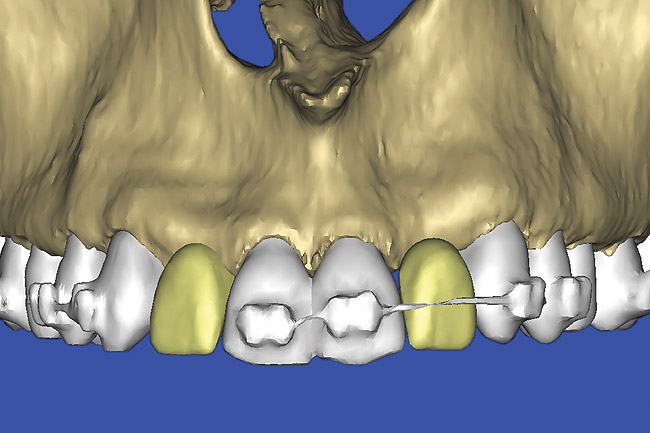

Figure 12  SOFTWARE IMAGING The 3D reconstruction showed the facial concavities and root eminences.

Figure 12

Figure 13  SOFTWARE IMAGING This allowed for evaluation of virtual implant placement to ensure the facial cortical plate was not perforated.

Figure 13

After the basic plan had been established, it was re-evaluated using interactive 3D images. The reconstructed 3D view of the maxilla clearly illustrated the extent of the bilateral facial concavities, and the root eminences of the adjacent and posterior teeth (Figure 12). The placement of the virtual implants then was evaluated to ensure that the facial cortical plate was not perforated (Figure 13). The implants were labeled individually as “7” and “10,” with the simulated yellow abutment projection indicating the facial-lingual inclination through the bone to the level above the incisal edge of adjacent teeth. The ability to gain a better understanding of these individual root forms cannot be underestimated. The dental literature has suggested certain parameters for placing implants near teeth and implants next to other implants. However, there is little scientific 3D documentation to support these suggested rules.5-10 The use of an interactive treatment-planning software application permits closer scrutiny of previously difficult-to-visualize areas, and can now be used to redefine perceptions of spatial positioning of implants, especially when in close proximity to natural tooth roots, vital anatomy, and adjacent implants.27-29